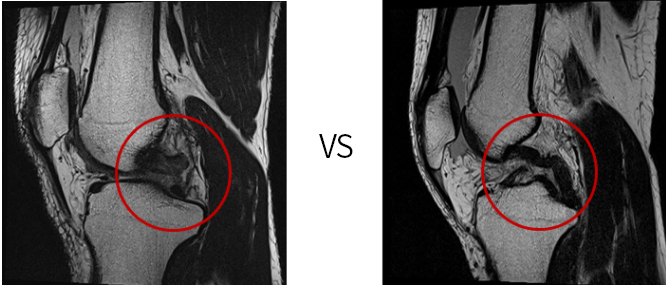

끊어진 상태인 후방십자인대(MRI)

늘어난 상태인 후방십자인대(MRI)